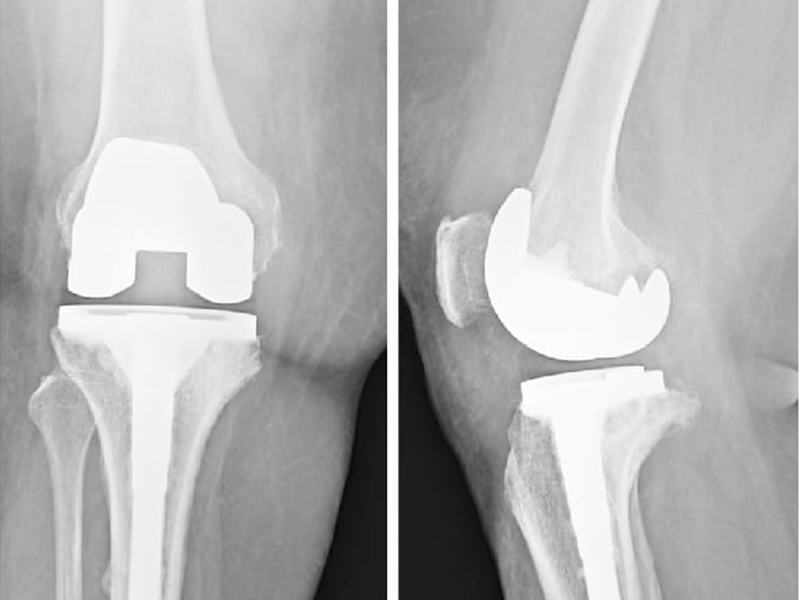

Knee replacement, also known as knee arthroplasty, is a surgical procedure to replace damaged or worn-out parts of the knee joint with artificial components (implants). It is designed to relieve chronic knee pain, restore mobility, and improve quality of life for patients suffering from knee conditions that have not responded to non-surgical treatments.

Total Knee Replacement (TKR)

• The entire knee joint is replaced with artificial components, including the lower part of the thigh bone (femur), the top of the shin bone (tibia), and the kneecap (patella).